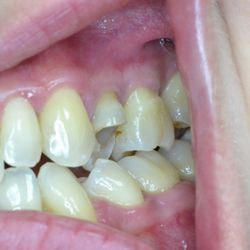

Ο 43χρονος αυτός ασθενής προσήλθε στο ιατρείο μας με έντονες αποτριβές των προσθίων και οπισθίων δοντιών του.

Ο αιτιολογικός παράγοντας για την καταστροφή της οδοντικής του ουσίας ήταν τα γαστρικά οξέα λόγω της χρόνιας γαστρο-οισοφαγικής παλινδρόμησης που παρουσίαζε.

Τα πρόσθια δόντια του αποκαταστάθηκαν με χτίσιμο σύνθετης ρητίνης επί τόπου ενώ τα οπίσθια δόντια του αποκαταστάσθηκαν με εργαστηριακά κατασκευασμένα επένθετα σύνθετης ρητίνης